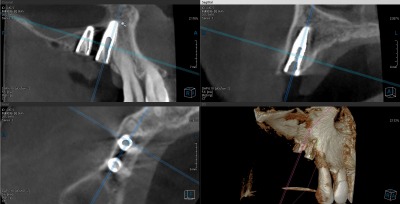

先月左の上はすでにインプラントを2本入れまして、今日は右上に2本のインプラントを入れました。

鼻腔が近くて当初1本の予定でしたが、歯肉側に少し骨を造って (GBR) 2本にしました。ギリギリでした。

期間をかけて、鼻腔に骨を造る場合(サイナスリフト)もありますが、今回は早く噛めるようにまずはできる所からしました。